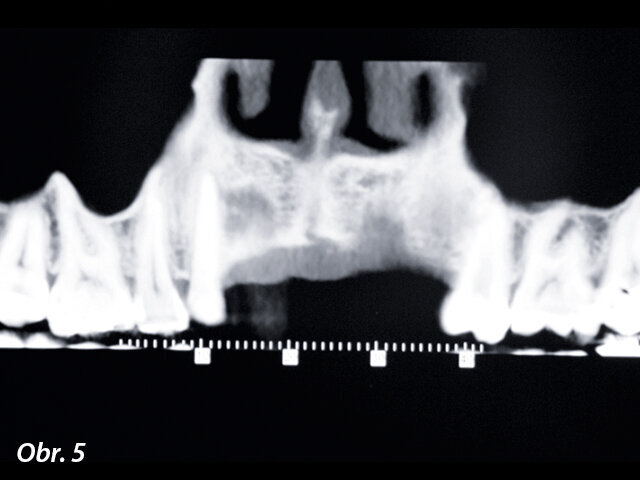

Tři měsíce po odstranění implantátů bylo provedeno klinické a radiologické vyhodnocení. To ukázalo další podstatný úbytek vertikálního rozměru i objemu kosti (obr. 5). Podstatný úbytek vertikálního rozměru kosti se s ohledem na nahodilou regeneraci gingivy obtížně koriguje. Bylo proto rozhodnuto augmentovat objem kosti štěpem odebraným z brady.

Oblast po odstranění implantátu vykazovala ještě větší úbytek objemu kosti.